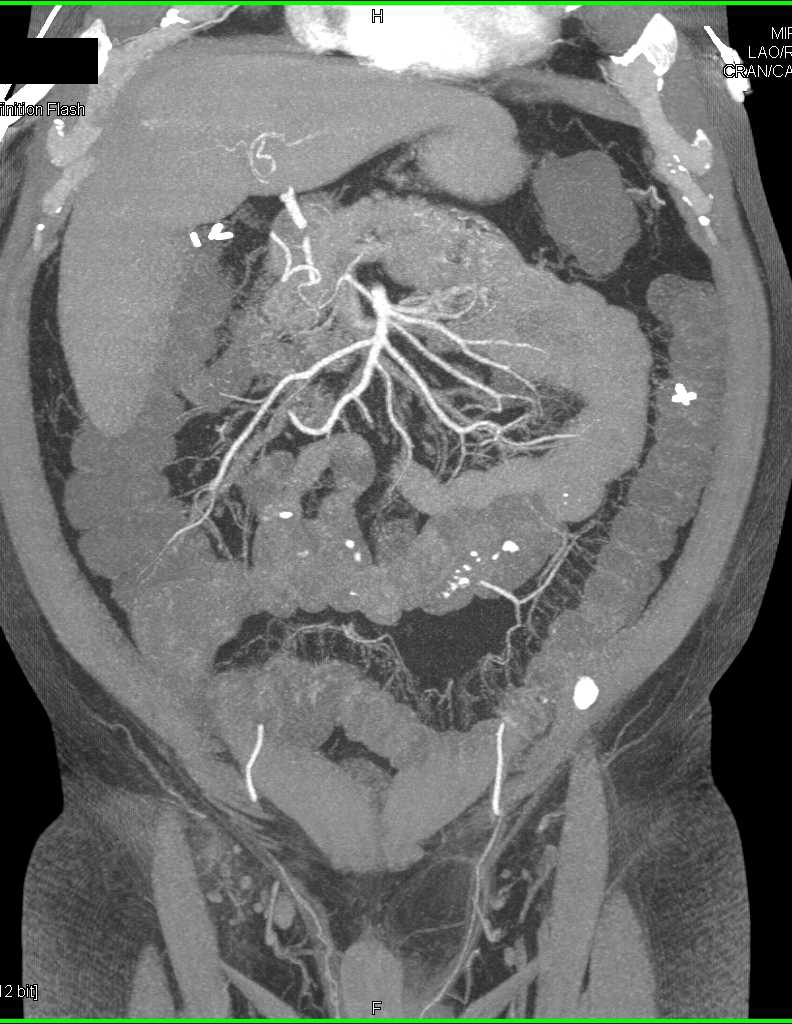

Bilateral Femoral Deep Vein Thrombosis (DVT)